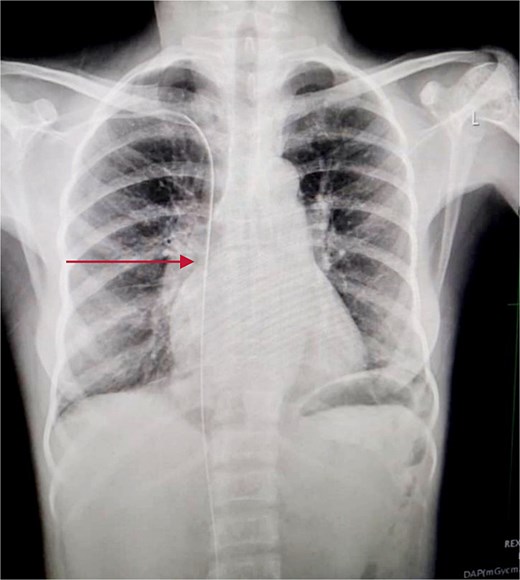

Chest and abdominal X-rays revealed the guide wire extending from the right subclavian vein through the superior vena cava (SVC), right atrium, and inferior vena cava (IVC) to the proximal right femoral vein (Figs 5 and 6).

Plain abdominal X-ray extending from the IVC through the right iliac vein to the right femoral vein.